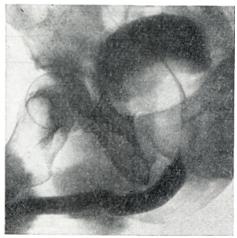

Рис. 6.

Симптом «удлинения мочеиспускательного канала» (уретроцистограмма)

Рис. 7.

Симптом «клинка сабли»; дно мочевого пузыря приподнято, виден удлиненный задний отдел мочеиспускательного канала (уретроцистограмма).

Применяют экскреторную урографию, цистографию и уретроцистографию; наиболее рациональна лакунарная уретроцистограмма по Кнайзе и Шоберу (рис. 4). Кислород, введенный по катетеру в количестве 150—200 мл, растягивает мочевой пузырь в виде купола. Введенное вслед за кислородом жидкое контрастное вещество (20% раствор сергозина в количестве 20 мл) располагается в области дна мочевого пузыря, выявляя внутрипузырный рост аденомы предстательной железы. Этим методом определяют ряд типичных рентгенологических симптомов: «берета» (рис. 5), удлинения мочеиспускательного канала (рис. 6), «клинка сабли» (рис. 7), приподнятого дна.

Экскреторная урография, помимо определения функции почек, указывает на состояние нижних отрезков мочеточников, которые крючкообразно приподнимаются кверху, давая изображение «рыболовного крючка» (рис. 8). Рентгенологическое исследование выявляет также сопутствующие заболеванию камни и дивертикулы.